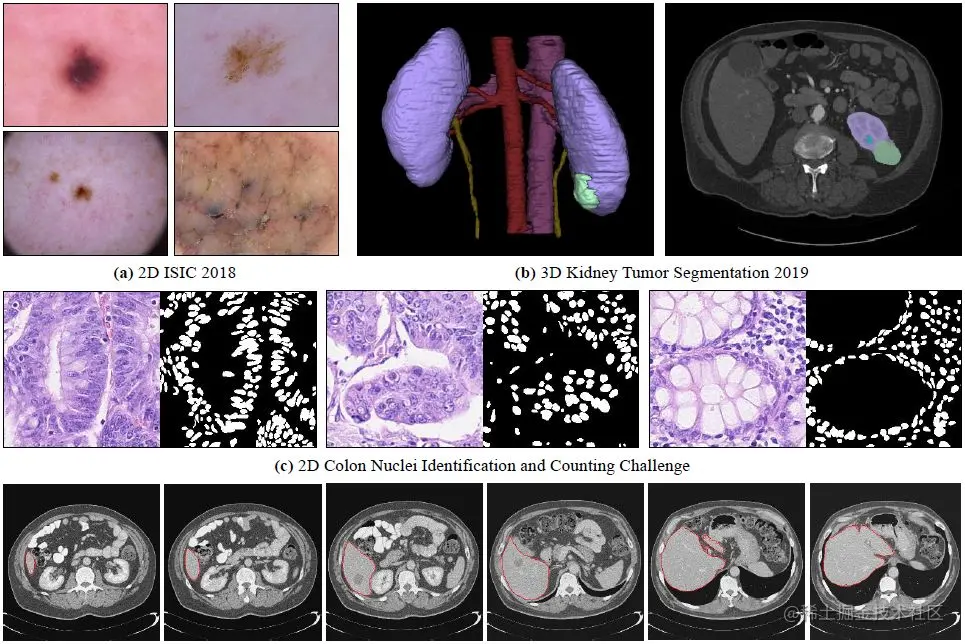

• 2022.09.21 『数据增强』 Deep Learning for Medical Image Segmentation: Tricks, Challenges and Future Directions

⚡ 论文:Deep Learning for Medical Image Segmentation: Tricks, Challenges and Future Directions

论文时间:21 Sep 2022

领域任务:Data Augmentation, Domain Adaptation, 数据增强域自适应

论文地址arxiv.org/abs/2209.10…

代码实现github.com/hust-linyi/…

论文作者:Dong Zhang, Yi Lin, Hao Chen, Zhuotao Tian, Xin Yang, Jinhui Tang, Kwang Ting Cheng

论文简介:Over the past few years, the rapid development of deep learning technologies for computer vision has greatly promoted the performance of medical image segmentation (MedISeg)./在过去的几年里,计算机视觉深度学习技术的快速发展大大促进了医学图像分割(MedISeg)的性能。

论文摘要:在过去的几年里,计算机视觉深度学习技术的快速发展极大地促进了医学图像分割(MedISeg)的性能。然而,最近的MedISeg出版物通常集中在对主要贡献的介绍上(如网络架构、训练策略和损失函数),而不知不觉地忽略了一些边缘的实现细节(也称为 "技巧"),导致了不公平的实验结果比较的潜在问题。在本文中,我们针对不同的模型实施阶段(即预训练模型、数据预处理、数据增强、模型实施、模型推理和结果后处理)收集了一系列MedISeg技巧,并通过实验探索这些技巧对一致的基线模型的有效性。与那些只基础地关注分割模型的优势和局限性分析的论文驱动的调查相比,我们的工作提供了大量扎实的实验,在技术上更具有可操作性。通过对具有代表性的二维和三维医学图像数据集的大量实验结果,我们明确地阐明了这些技巧的效果。此外,基于所调查的技巧,我们还开源了一个强大的MedISeg资源库,其中的每个组件都具有即插即用的优势。我们相信,这项里程碑式的工作不仅完成了对最先进的MedISeg方法的全面和补充调查,而且还为解决未来的医学图像处理挑战提供了实用指南,包括但不限于小数据集学习、类不平衡学习、多模式学习和领域适应。该代码已在以下网站发布:github.com/hust-linyi/…